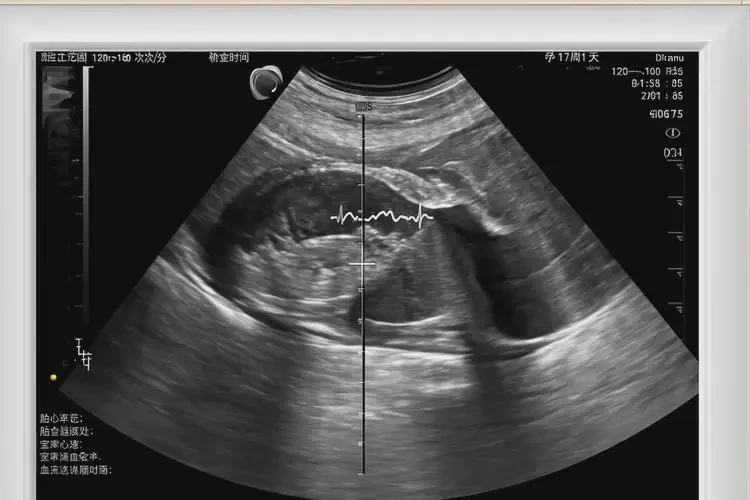

孕17周1天胎心率76寶寶還能要嗎

胎心率76次/分鐘在孕17周1天屬于異常情況,需要進一步評估和監(jiān)測。

孕17周1天的正常胎心率范圍通常在140-170次/分鐘之間。胎心率76次/分鐘明顯低于正常范圍,可能提示胎兒存在某些問題,如胎兒窘迫、心臟異常或其他健康問題。僅憑一次胎心率測量結(jié)果無法確定胎兒的健康狀況,需要結(jié)合其他監(jiān)測數(shù)據(jù)和醫(yī)生的評估來做出判斷。